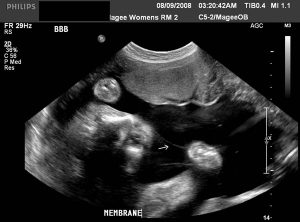

"Wir waren so aufgeregt, dass wir uns kaum enthalten konnten. Wir nannten unsere Mütter und sagten: 'Guten Morgen Nanny' ', Danielle erzählte. Und dann holte ein Scan in sieben Wochen auf, dass das Ei Split-Danielle-Zwillinge hatte. Es gab jedoch eine alarmierende Entwicklung. Es gab einen spürbaren Größe zwischen den Zwillingen, obwohl jeder Fötus nicht größer als eine Blaubeere war.

Die rote Flagge

Aber um 16 Wochen wurden die Dinge ernst. Ärzte hatten vor dem Twin-to-Twin-Transfusionssyndrom früher angedeutet, aber als Teddys Blase auf Scans "abwesend" wurde, war dies ein sicheres Zeichen von TTTs. Danielle sagte: "Eine verschwundene Blase im Donor Twin ist eine rote Flagge. Mit 20 Wochen hatten wir die schlechtesten Nachrichten. "

Twin to Twin Transfusion-Syndrom ist, wenn identische Zwillinge, die eine Plazenta teilen, eine ungleiche Verteilung von Nährstoffen davon abhalten. Nur einer der Zwillinge erhält das Blut und die Nährstoffe im Fülle. Dies kann zu Herzinsuffizienz führen. Der Zwillingspender empfängt unzureichende Blut- und Nährstoffe, die ihr Wachstum verlangsamen. Ihre Blase beginnt zu verschwinden und ihre Überlebenschancen verringern sich.